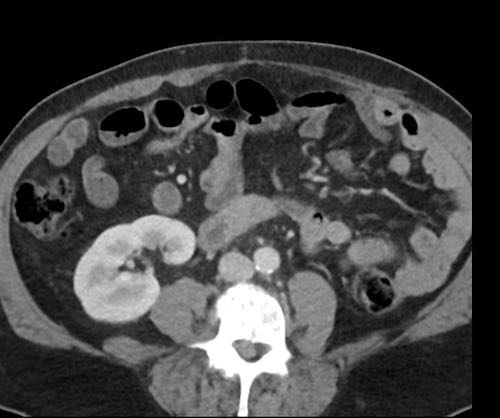

Cuộn xem ảnh CT

Ca lâm sàng 1

Cuộn qua các lát cắt.

Bạn có thể phát hiện tất cả các tổn thương cấy ghép phúc mạc không?

Bệnh nhân này đã được phẫu thuật và toàn bộ phúc mạc được ghi nhận phủ kín bởi các tổn thương u dạng kê.